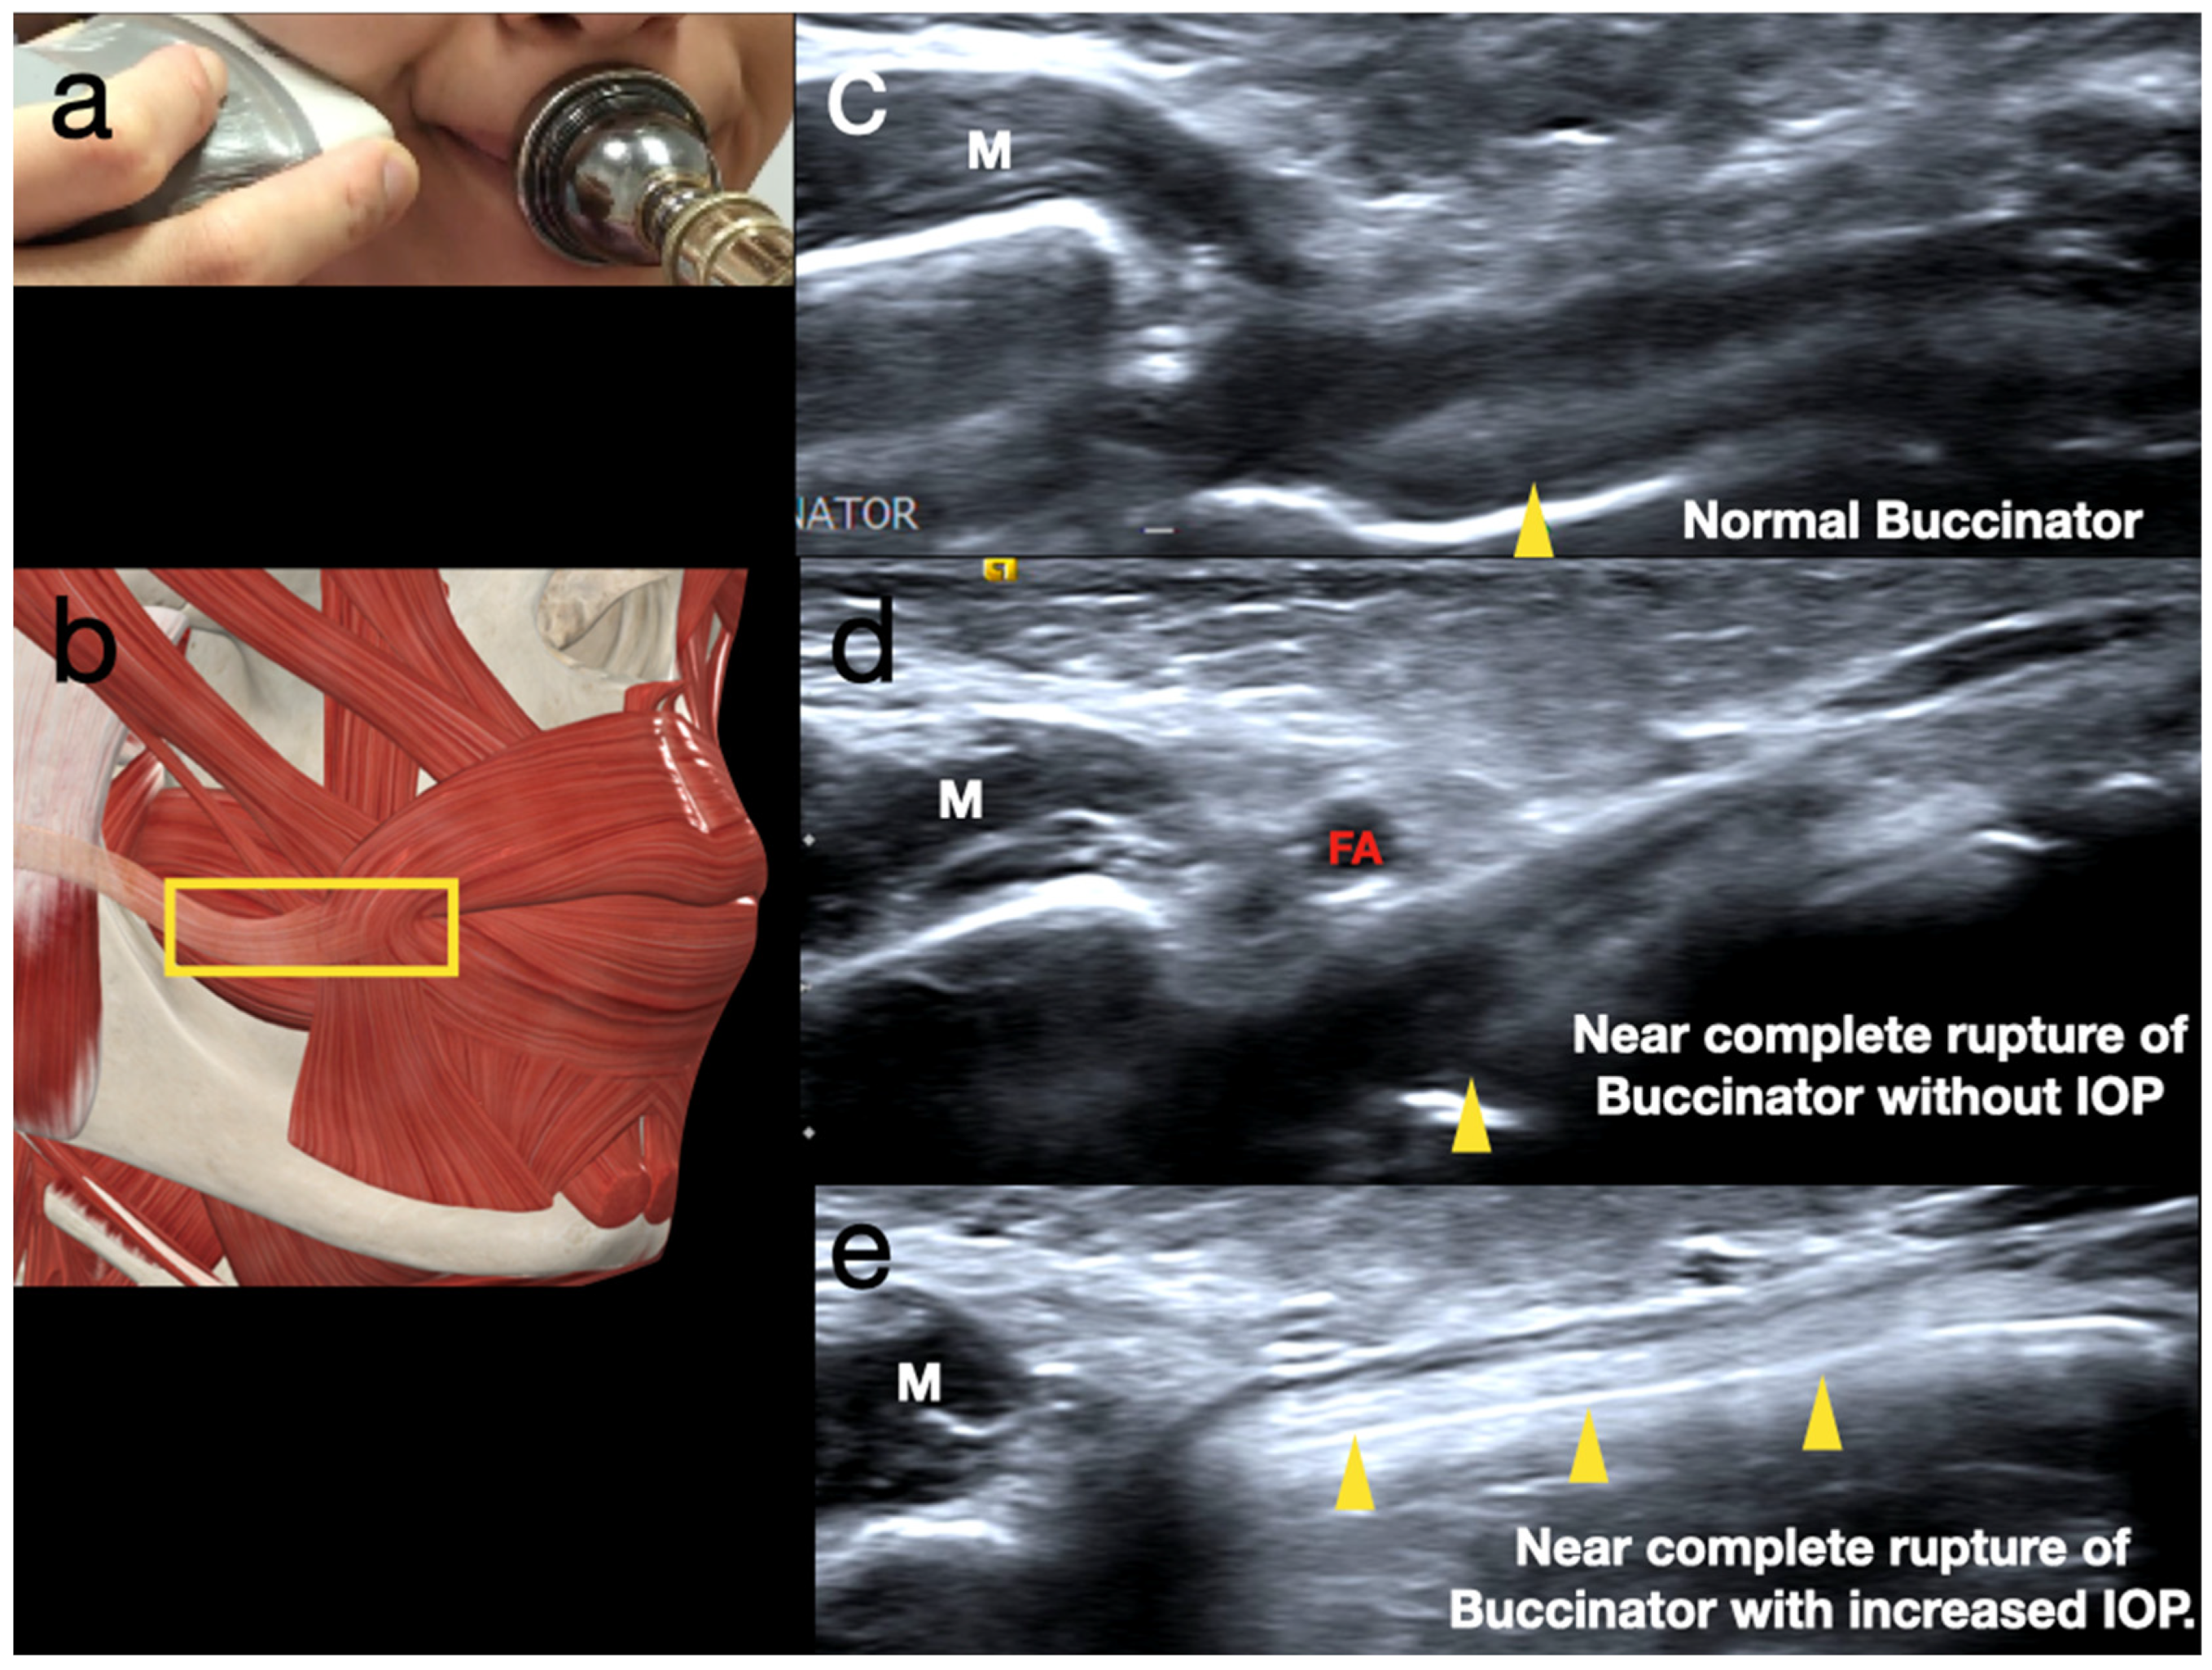

2.1. Sonoanatomy of Peri-Oral Musculature and Fascia System Concerning Embouchure

2.2. Scanning Protocol for the Embouchure in Wind Players